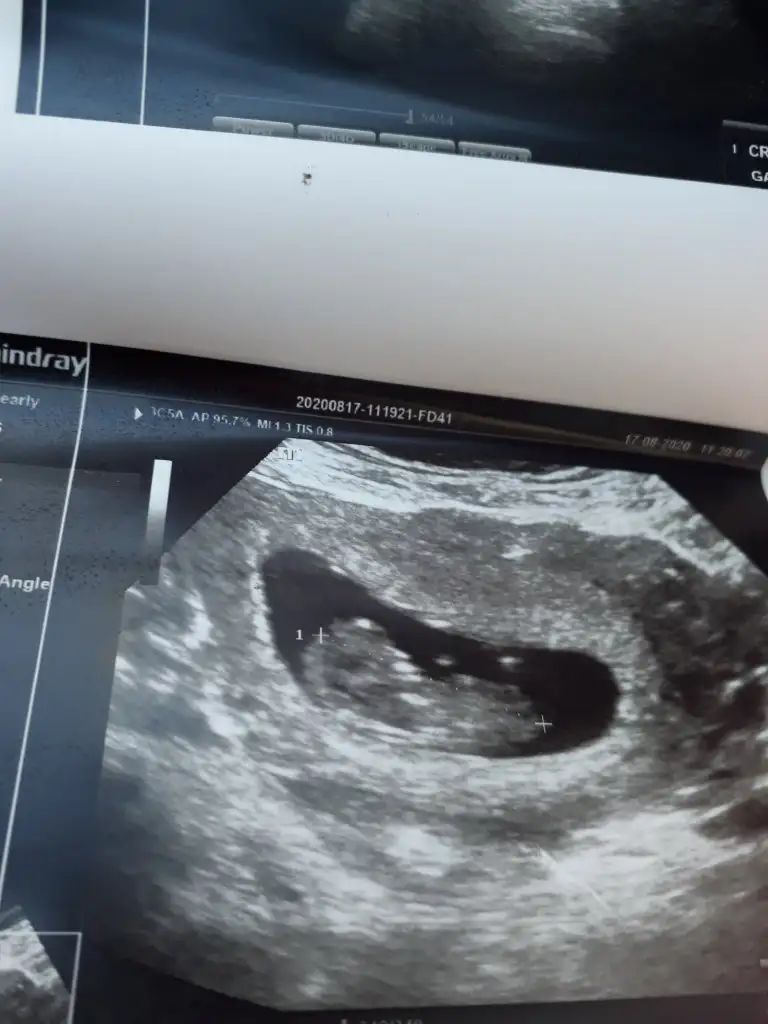

Gulum hamilelik iyi gidiyor hamd olsun 9hafta 4 gunluk ama doktor 10 hafta 5 gunluk gorunuyor dedi hatta iki tane ultrason kagidi verdi birinde 10 +5 digerinde 11 yaziyor nub falan gorunmuyormu kizlar

Yok nub göremedim net değil cnmGulum hamilelik iyi gidiyor hamd olsun 9hafta 4 gunluk ama doktor 10 hafta 5 gunluk gorunuyor dedi hatta iki tane ultrason kagidi verdi birinde 10 +5 digerinde 11 yaziyor nub falan gorunmuyormu kizlar

Zaten ben sizden 11 12 13 haftalar istedim (tutmayabilir) yazdimanlamadigim, nub genital bilge olusana kadar gorulen birsey, peki benim 14 uncu haftada neden hala nub gorunuyr.Genital bolge olusmus olmasi gerekmiyormu

Erkek gibiHa pardon. Simdi yolluyorum. Bu resim 5 agustosun. 6 mayis son adetim, yani resimde 13.0 haftalik degilmi?